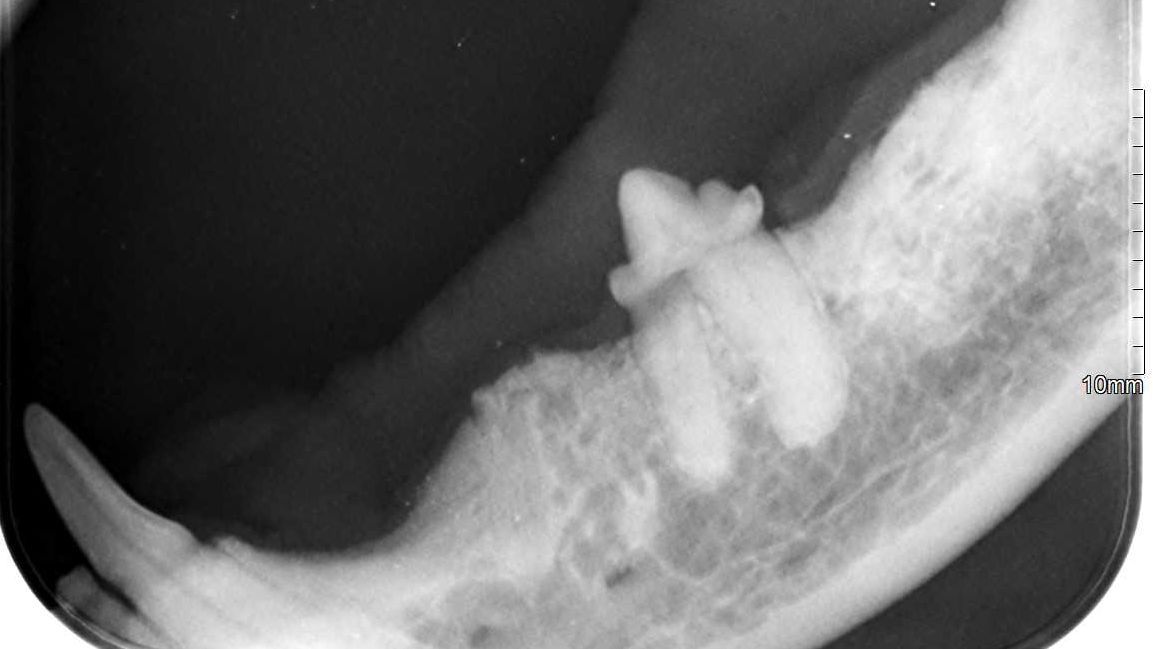

Nicht alle Zahnerkrankungen bei Hunden und Katzen sind sofort sichtbar. Während sich Zahnstein und Zahnfleischerkrankungen schon an der Oberfläche erkennen lassen, können die wahren Probleme oft tiefer, im Inneren des Zahns oder im Kiefer liegen. Mit dem bloßen Auge sind diese meist nicht erkennbar - auch nicht für uns Tierärzte. Hier können Röntgenbilder schnell Klarheit verschaffen.

- Versteckte Zahnfrakturen: Manchmal brechen Zähne tief ab und über den abgebrochenen Zahn wächst Zahnfleisch. Von außen ist dies nicht erkennbar, in der Tiefe kann der Wurzelrest aber für Entzündungen und Schmerzen sorgen.

- Parodontitis: Diese Entzündung des Zahnhalteapparats beginnt oft unscheinbar, ist jedoch in fortgeschrittenen Stadien meist schmerzhaft und kann zum Eindringen von Keimen in den Körper, zu Knochenrückgang und Abszessen führen (siehe unten).

- Knochenrückgang (Osteolyse): Durch Zahnstein, Zahnfleisch- oder Zahnwurzelentzündungen, Parodontitis oder auch bei älteren Tieren kann sich die Knochensubstanz um die Zähne herum zurückziehen. Dies führt zu wackelnden Zähnen.

- Resorptive Läsionen (auch "FORL") bei der Katze: Diese sehr schmerzhaften Veränderungen sind bei Katzen weit verbreitet und lassen sich oft erst im fortgeschrittenen Stadium mit bloßem Auge erkennen, obwohl sie schon viel früher starke Schmerzen verursachen, da sie zu einer langsamen Auflösung des Zahns führen. Im Röntgen lassen sich diese Veränderungen frühzeitig erkennen.